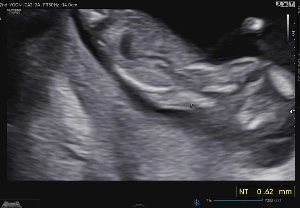

그리고 목투명대 검사를 했다. 선생님은 "얘는 보지도 않아도 정상"이라고 말씀하시며 목투명대 길이를 재셨다. NT(목투명대) 길이는 0.62mm.

*NT는 보통 3-5mm 이하 일 때 저위험으로 보고, 그렇다고 하더라도 무조건 정상이라는 게 아니라 확률상 특별한 문제가 없을 확률이 높다는 것이다.

정상입니다.